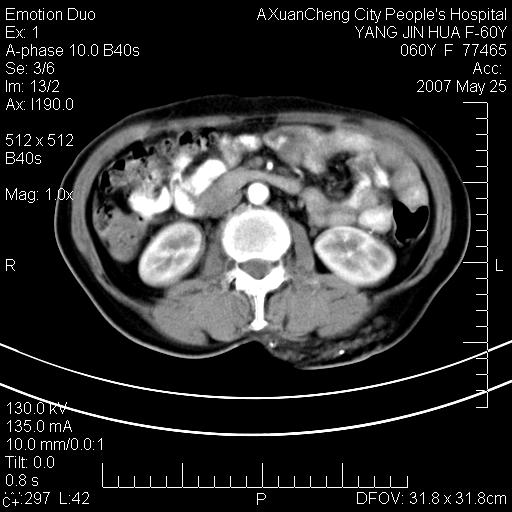

发现左侧腰背部包块40余年,逐渐长大,质软,局部表面可见扩张的血管影

左背部皮下良性肿瘤,密度不均,边界不清,内有脂肪、钙化,增强扫描无明显强化,血管平滑肌脂肪瘤?进一步诊断有困难,建议穿刺活检。

左侧背部皮下混杂密度肿块,结构较疏松,边缘欠光整,内有多发斑点状钙化,考虑:皮下血管瘤。

这个病理增强扫描之前,我们是考虑是血管瘤,可是现在增强后一点强化都没有,还能考虑是血管瘤吗